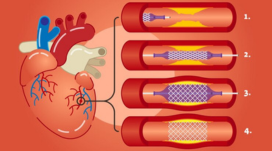

2 Stentless Angioplasty/ Metal less PCI( Percutaneous Coronary Intervention)

We have done 2 Stentless Angioplasty/ Metal less PCI( Percutaneous Coronary Intervention) in our centre ( 1 st time in this district )with Drug Eluting balloon in the last few days.

Drug-eluting balloons (DEBs) are primarily used to treat restenosis, especially in-stent restenosis (ISR) and de novo lesions, particularly in smaller vessels and situations where avoiding a stent is preferred. DEBs offer a way to deliver medication locally to the vessel wall to prevent re-narrowing after angioplasty. Specific Indications for DEBs: In-stent restenosis (ISR): DEBs are particularly useful in treating restenosis that occurs within previously implanted stents, especially bare-metal stents (BMS). De novo lesions: DEBs can be used to treat new blockages in coronary arteries, especially in situations where stent implantation is not ideal, like in small vessels or bifurcation lesions. Small vessel disease: DEBs are a good option when dealing with smaller coronary arteries where stent placement might be challenging or less optimal. Bifurcation lesions: In cases where a blockage occurs at a branch point of a coronary artery, DEBs can be used to avoid stenting both branches. Acute myocardial infarction (AMI): DEBs can be used in the setting of acute heart attacks, particularly when a stent is not immediately necessary. Femoropopliteal occlusive disease: DEBs are also used in the peripheral arteries, such as the femoropopliteal arteries, to treat blockages in the legs. High bleeding risk patients: DEBs may be preferred over DES in patients who cannot tolerate long-term dual antiplatelet therapy, according to some studies.